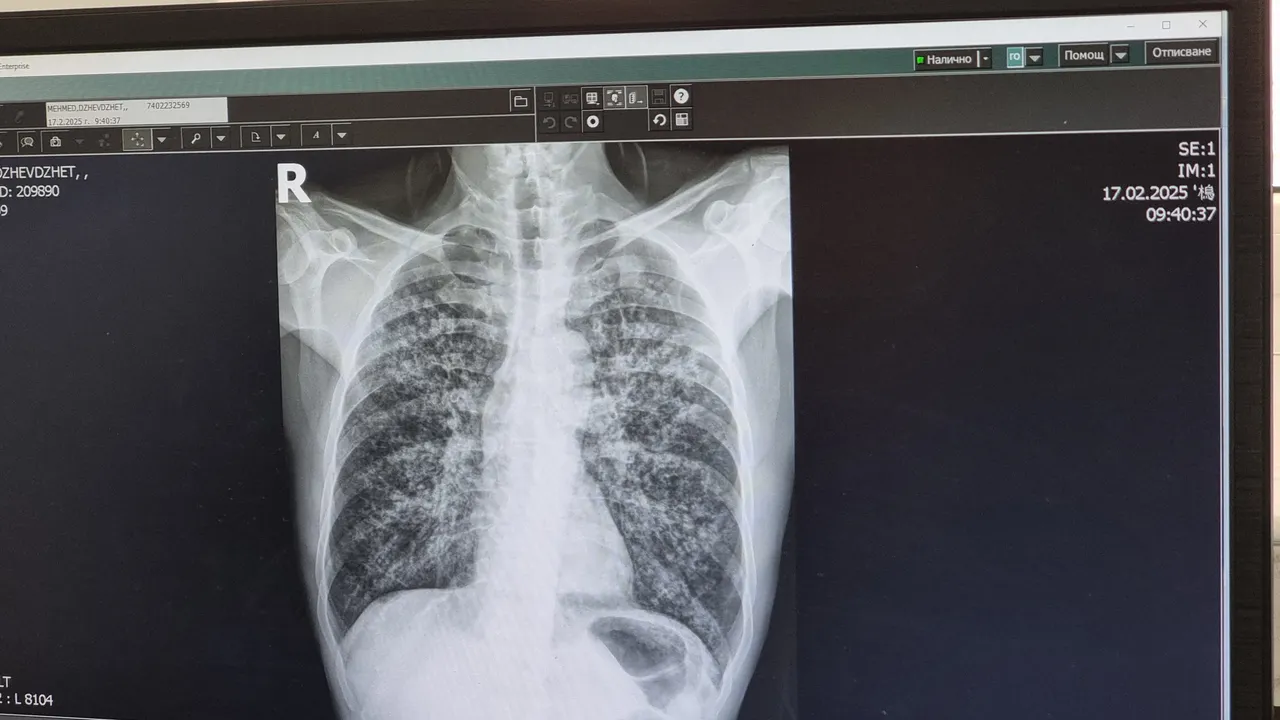

Безплатни прегледи за риск от туберкулоза в Плевен

Плевенската университетска болница "Д-р Георги Странски" организира кампания за оценка на риска от белодробна туберкулоза. За това съобщават от лечебното заведение, цитирани от БТА.

Всички процедури във връзка с кампанията ще бъдат напълно безплатни за участниците, независимо от здравноосигурителния им статут. Процедурата включва попълване на анкети, медицински прегледи и консултации със специалисти. При необходимост медицинският екип ще извършва и допълнителни изследвания.

Кампанията за безплатни прегледи за оценка на риска от туберкулоза се организира четири пъти годишно. Последната се състоя през септември.